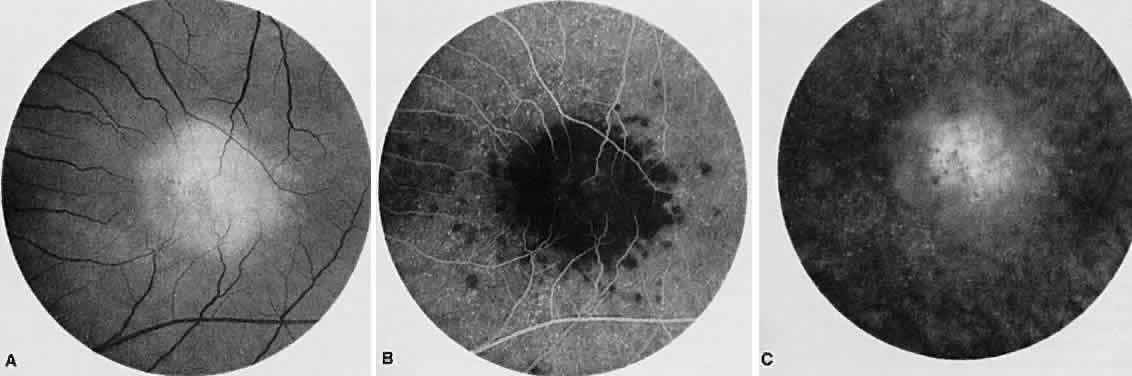

ACUTE MULTIFOCAL POSTERIOR PLACOID PIGMENT EPITHELIOPATHY

Acute multifocal posterior placoid pigment epitheliopathy is a bilateral systemic disease that generally affects young, healthy adults, often after a flulike viral illness. It presents as a rapid, painless loss of vision, which usually is bilateral. The characteristic findings of the disease are deep, multiple, discrete, flat, creamy-white subretinal lesions, usually centered in the posterior pole. Associated vitreous cells, serous retinal detachments, disc edema, and vasculitis have been reported. Shortly after the onset of symptoms, the acute yellow placoid lesions resolve, showing irregular deposition of pigmentation without corresponding atrophy of the choroid. Associated but infrequent systemic signs include hematuria, hearing loss, erythema nodosum, thyroiditis, and cerebral vasculitis. In general, vision returns to normal even when significant retinal pigment epithelial mottling is present. SRNV is a rare complication. AMPPPE rarely recurs; however, there are some unilateral cases in which the second eye may become affected months later. When unilateral cases occur, it is necessary to differentiate acute multifocal posterior placoid pigment epitheliopathy from serpiginous choroiditis.

Angiographically, the creamy lesions initially block the choroidal background fluorescence. Later there is staining that is widely and evenly distributed (Fig. 13). The cause of the initial blocking is controversial. Some believe that this disorder is a systemic vasculitis with nonperfusion of the choriocapillaris. In support of this view, choroidal vessels occasionally can be seen through the hypofluorescent lesions.42,43 However, others believe that opaque retinal pigment epithelial cells block the choroidal fluorescence. The lesions do not correspond to the anatomy of the choriocapillaris and do not stain from the periphery as would be expected from the normal perfused neighboring choriocapillaris.44 Some cases of AMPPPE have been associated with serous detachment, showing late subretinal pooling of fluorescence. Old lesions show both hyperfluorescence and hypofluorescence depending on the retinal pigment epithelial integrity. Visual acuity usually returns to normal, even with clinically significant retinal pigment epithelial alteration.

Fig. 13. Acute multifocal posterior placoid pigment epitheliopathy. A. Red-free photograph of multifocal lesions at the level of the retinal pigment epithelium during the acute stage. B. Fluorescein angiography shows the multiple areas of hypofluorescence early in the arteriolar-venous phase. C. In the late venous phase, the hypofluorescent lesions have become hyperfluorescent.

ICG angiography shows well-demarcated areas of hypofluorescence of the acute and subacute lesions, especially in the late phases of the study. Similar findings are seen in healed AMPPPE lesions, but they tend to be smaller in size than in the acute lesions. The cause of the hypofluorescence seen with ICG angiography also is debatable. RPE edema, partial choroidal vascular occlusion, or complete choroidal vascular occlusion has been proposed, but none have been proved as the etiologic mechanism for the blockage.45